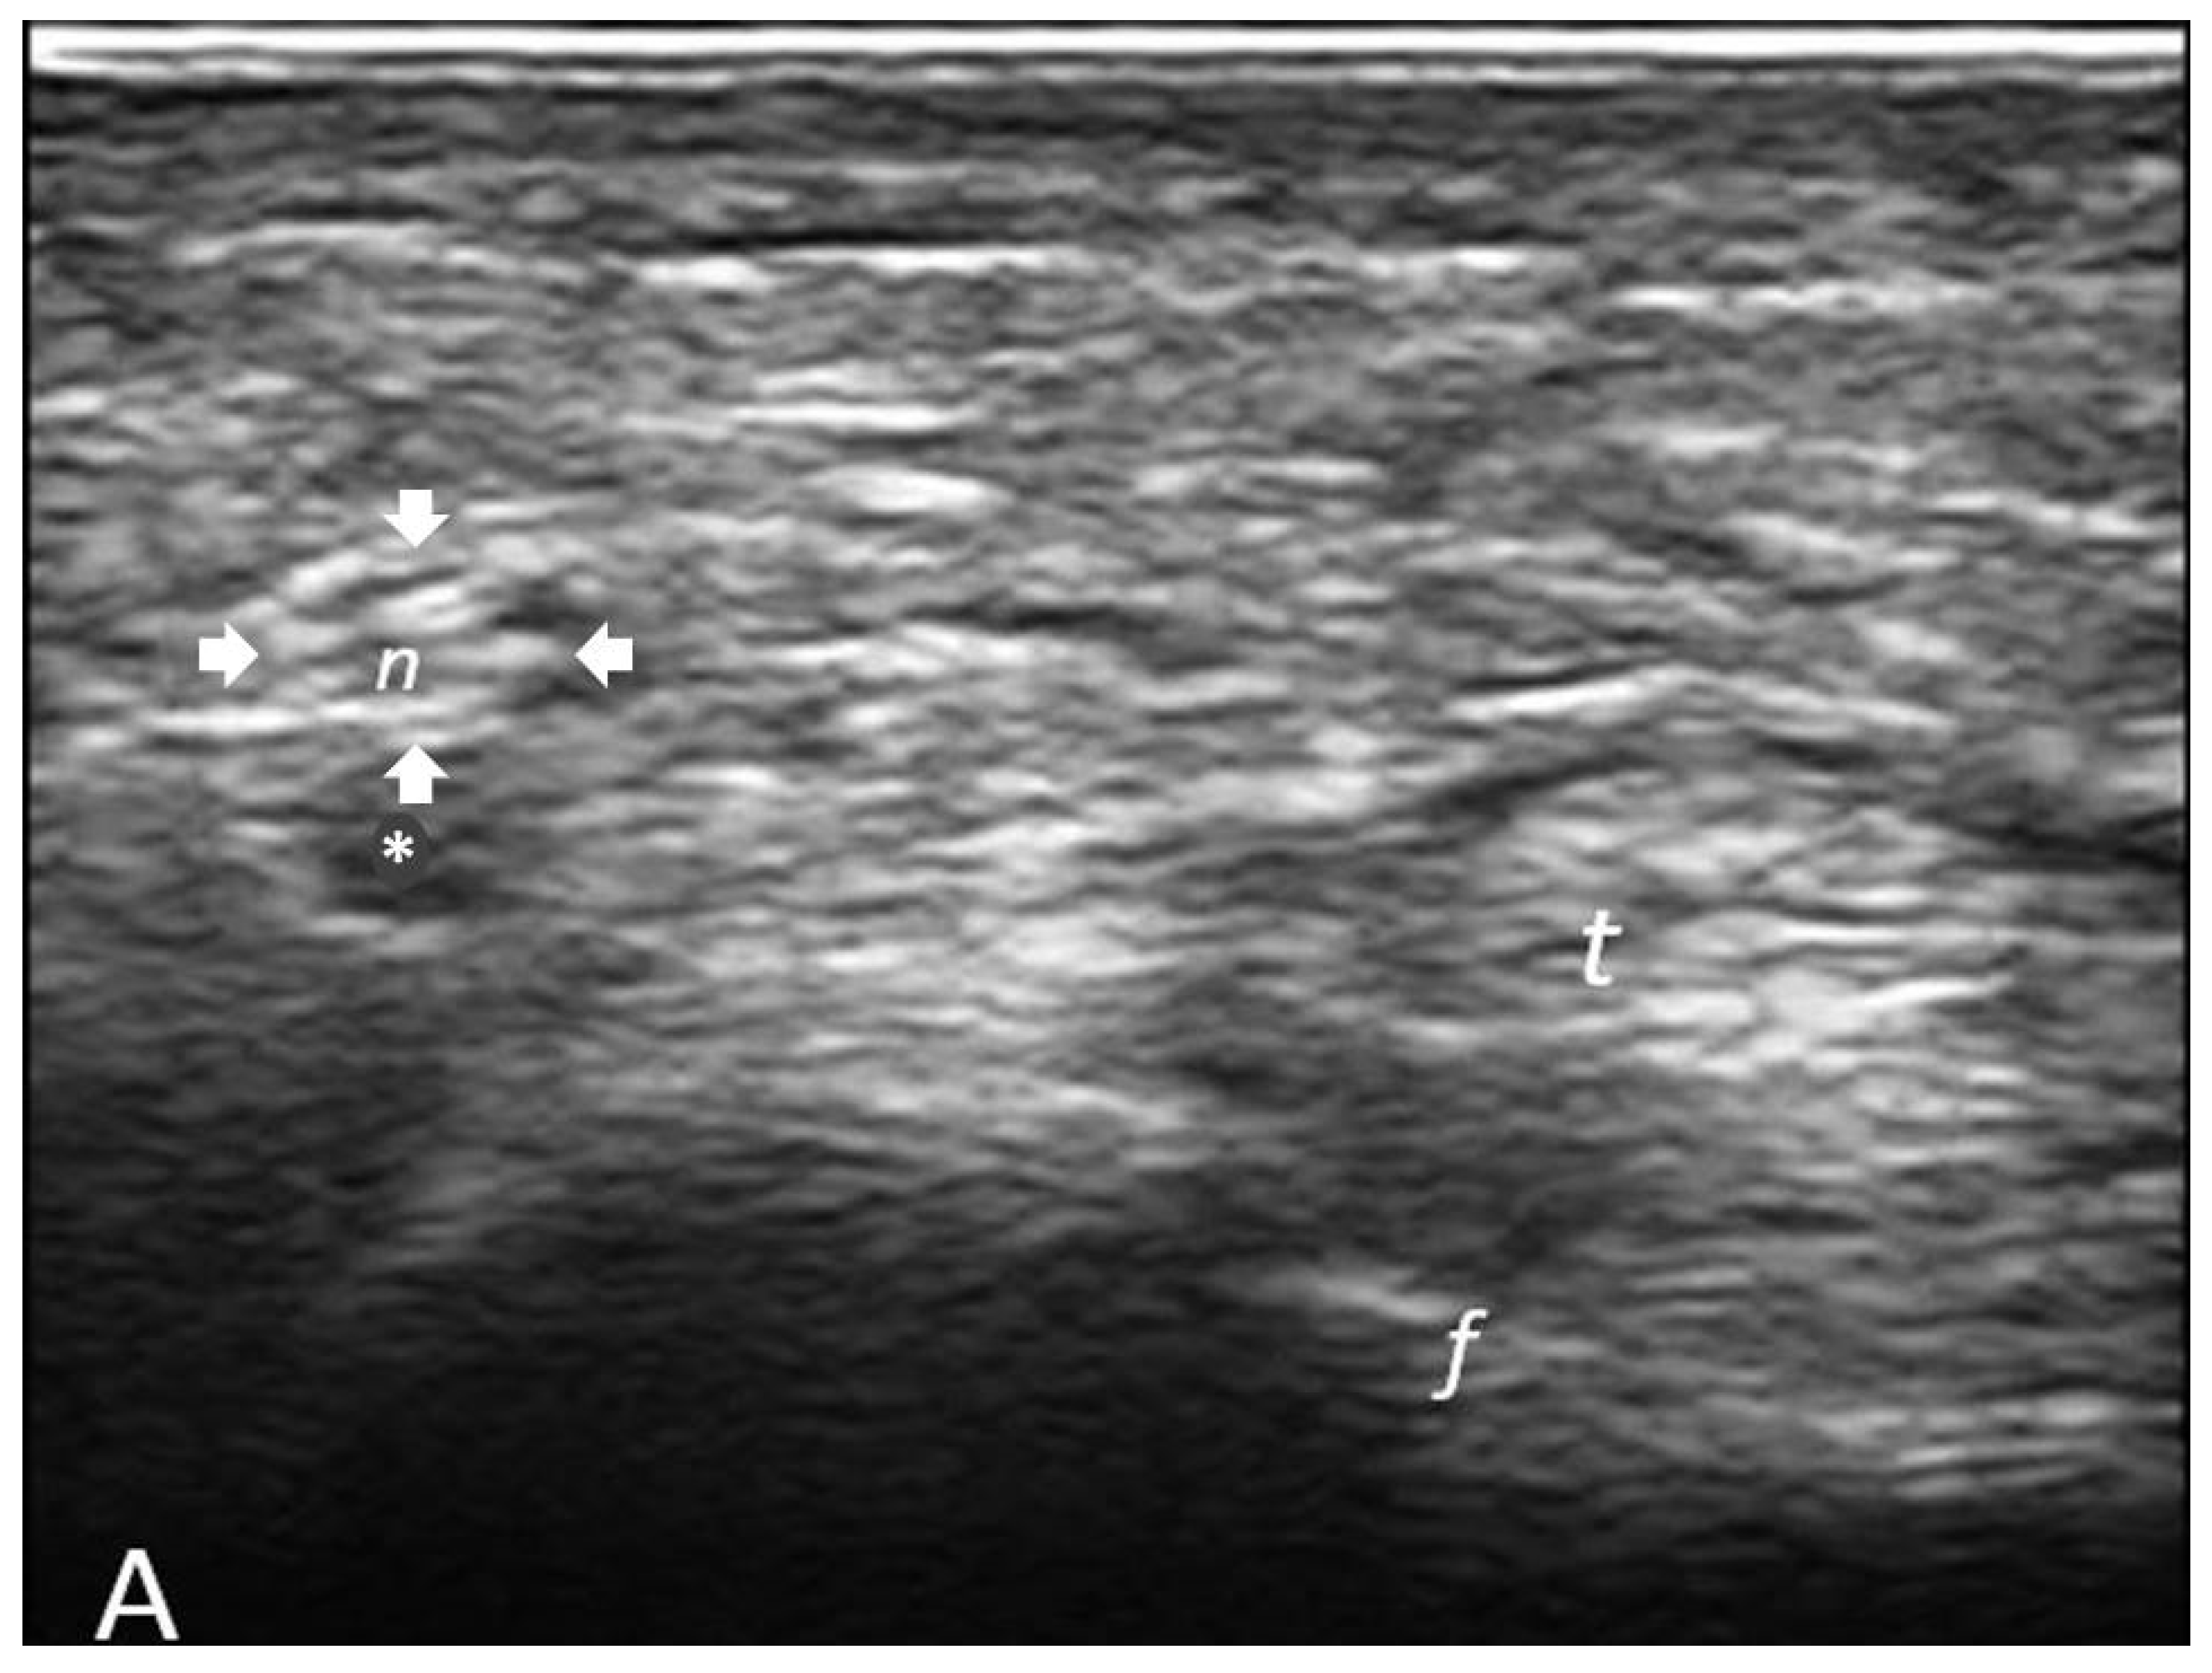

2.3.2. Determination of Cross-Sectional Area (CSA) of Palmar Digital Nerves